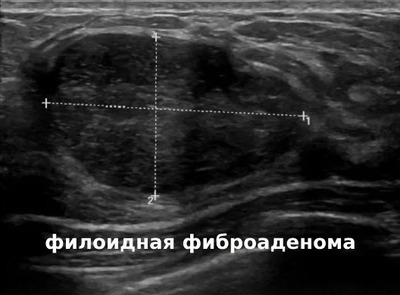

3️⃣ Ультразвуковое исследование молочных желез (УЗИ).